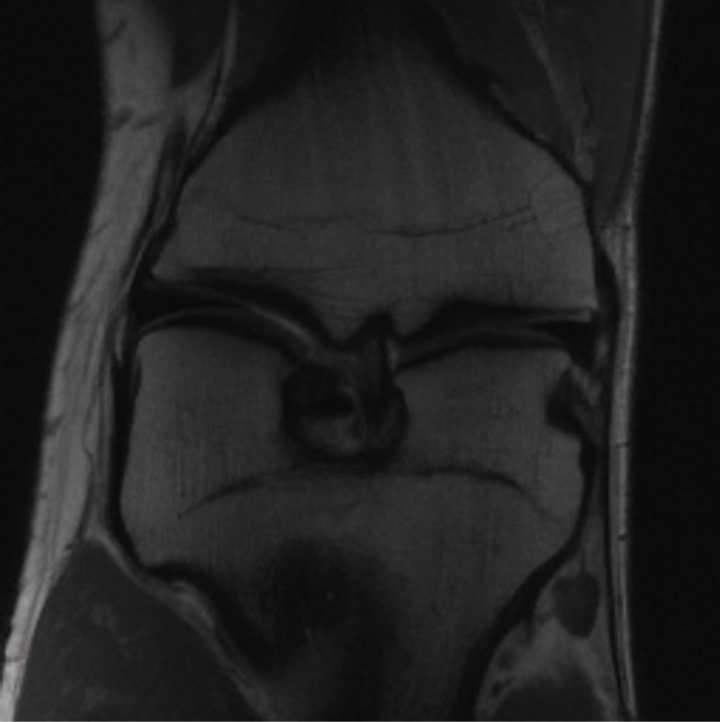

Notably, X-Diffusion achieves state-of-the-art dB for a few input slices while baselines require more than 60 input slices to achieve similar performance (Figure 7). The margin is more than 12 dB PSNR for the 1-slice input in both the BRATS and the UK Biobank benchmarks (see Table 1 and Figure 6). For reference, two randomly sampled MRIs from UK Biobank would have a PSNR of 15.95 dB 0.36 (on 4800 randomly sampled examples). Omitting the preprocessing step of alignment DXA to MRI, leads to a drop of PSNR on average by 2.87 dB (29.01 dB 26.14 dB). The slices from 3D reconstructed volumes at varying depths and axis of rotation, visually match the ground truths for both brain and whole-body scans (see Figures 4 and 5 left). We also plot the error map (Figure 3) and the spread of the error (Figure 5 right) of such X-Diffusion generations to highlight the differences with the ground truth MRIs.

Preservation of Spine Curvature. For the spine segmentation on UK Biobank, we use a UNet++ model [83] with Dice Loss. We use a model trained to predict curves on DXA on UK Biobank [11]). We measure the Pearson correlation factor [11] of spine curvature measured on the generated MRIs where the input is a single MRI coronal slice, a single sagittal slice, or from the paired DXA, against the curvature of reference real MRIs of the same samples. The correlation coefficients are 0.89 for the coronal MRIs, 0.88 for the sagittal MRIs, and 0.87 for the DXAs on the test set of 308 human-annotated angles. We can then bin the curvature of the spines under different scoliosis categories based on human-annotated angles: mild: , moderate: , and severe . We show the results in Figure 8. This illustrates that the generated MRIs preserve the spine curvature from normal to severe scoliosis cases. Additional details about spine curvature are provided in supplementary material.

For the spine segmentation on UK Biobank, we use a UNet++ model [83] with Dice Loss. We use a model trained to predict curves on DXA on UK Biobank [11]. We show in Figure IX that generated MRIs preserve the spine curvature from normal to severe scoliosis cases. We also study the case when DXA is used to generate the MRIs and show in Figure IX how the correlation to real curvatures compares to the input MRI case. The curvatures of the MRI generated from the coronal plane match the DXA curvatures more than the curvatures generated from sagittal MRI. This is expected since the antero-posterior plane of DXA is equivalent to the coronal plane for MRIs. This also explains the greater Pearson’s correlation coefficient of the coronal MRI (0.89) and DXA-generated curvature (0.88) compared to sagittal-generated curvature (0.87) relative to the reference curvature on the coronal plane. We observe though that MRI generation using X-Diffusion from another plane than the conventional plane for scoliosis assessment is valid.